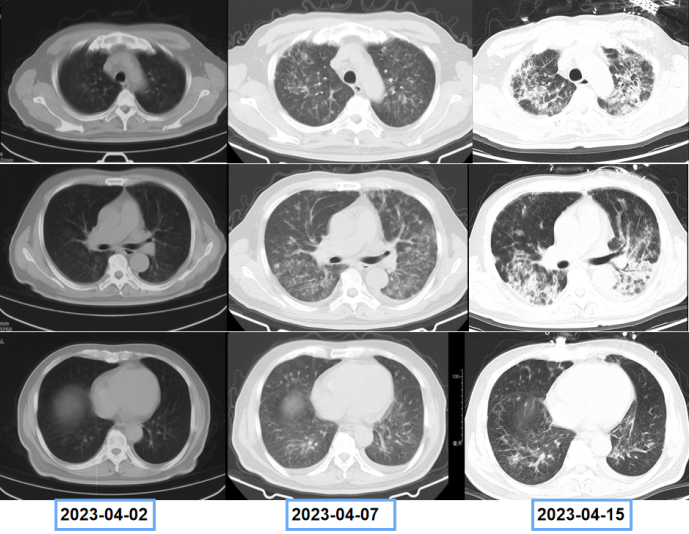

患者既往前列腺癌病史,双肺弥漫间质性病变,考虑肿瘤不能除外,遂于4月15日进一步行PET-CT(图4),结果显示:双肺多发病变,纵隔及双肺门淋巴结代谢增高,考虑炎症。前列腺代谢不均匀增高,符合前列腺癌表现。左侧耻骨及双侧坐骨骨质异常伴代谢增高,考虑转移。患者双肺病变较前快速进展(图5)

图5  患者胸部CT变化